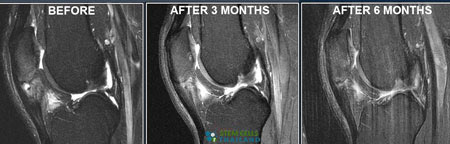

After Stem Cell Treatment for Sports Injuries

Depending on the severity of the injury, the healing process begins immediately upon the delivery of cells to the body. The most immediate relief can be felt in the lack of pain that occurs post-treatment. The effectiveness of the entire treatment protocol for injury-related neuropathy, stem cells for rotator cuff, and DDD will still mainly depend on the patient’s ability to follow post-treatment care coupled with foods that are good for joint health and a rehabilitation program to strengthen the areas that were affected.[1]